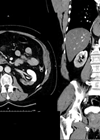

Case 1 A 76-year-old diabetic man with a long-term catheter presents to the Emergency Department with rigors and non-specific abdominal pain. He has an elevated white cell count (WCC) and C-reactive protein (CRP). An abdominal and pelvic CT scan was...